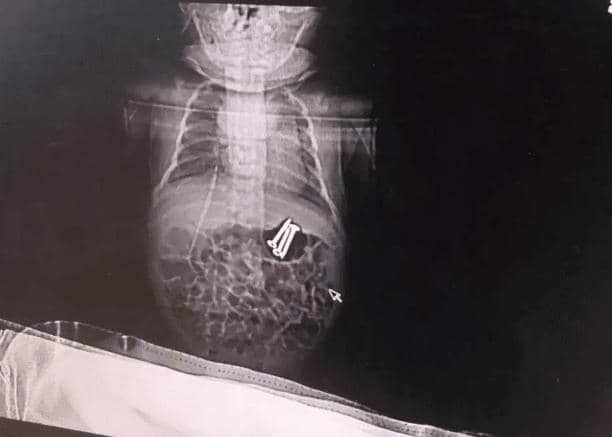

Seorang bayi berusia 37 hari dibawa ke rumah sakit Zhengzhou Children’s Hospital di China oleh mamanya karena mulutnya berbusa. Sang Mama mencurigai bayinya itu menelan sekrup yang disuapkan oleh kaka Si Bayi. Sang Kakak yang berusia 3 tahun, saat itu dimintai tolong Si Mama untuk menjaga adiknya.

Dokter Li Xiaoqin, kepala bagian gastroenterologi, memakai gastrocope untuk melihat bagian dalam perut Si Bayi. Lalu setelah memastikan lokasi benda asing itu, dokter memakai magnet untuk mengeluarkannya.

Menurut laporan The Sun, Si Bayi selamat setelah ketiga sekrup itu berhasil dikeluarkan dari dalam perutnya.